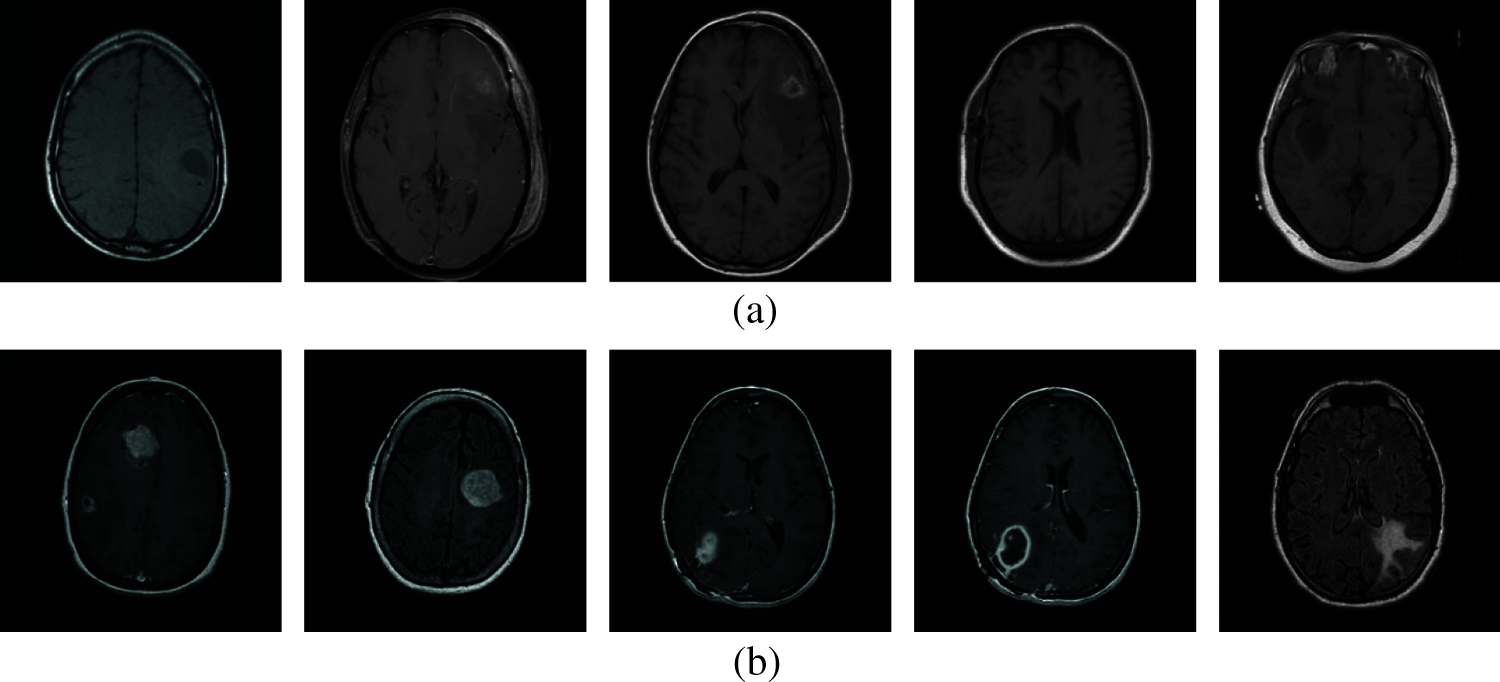

The superiority of the modified VGG architecture is demonstrated in this section. The REMBRANDT dataset [18–19] consists of MRI brain images of 130 patients which are downloaded freely [20]. The in-plane resolution of images is 256 × 256 pixels. The database consists of MRI images from normal and glioma patients. Samples from normal and abnormal images are shown in Fig. 6.

Figure 6: (a) Normal and (b) Abnormal

200 MRI images are randomly selected with 100 normal and 100 abnormal. The setting for database split-up for training and testing is shown in Tab. 2 which is used to evaluate the system.